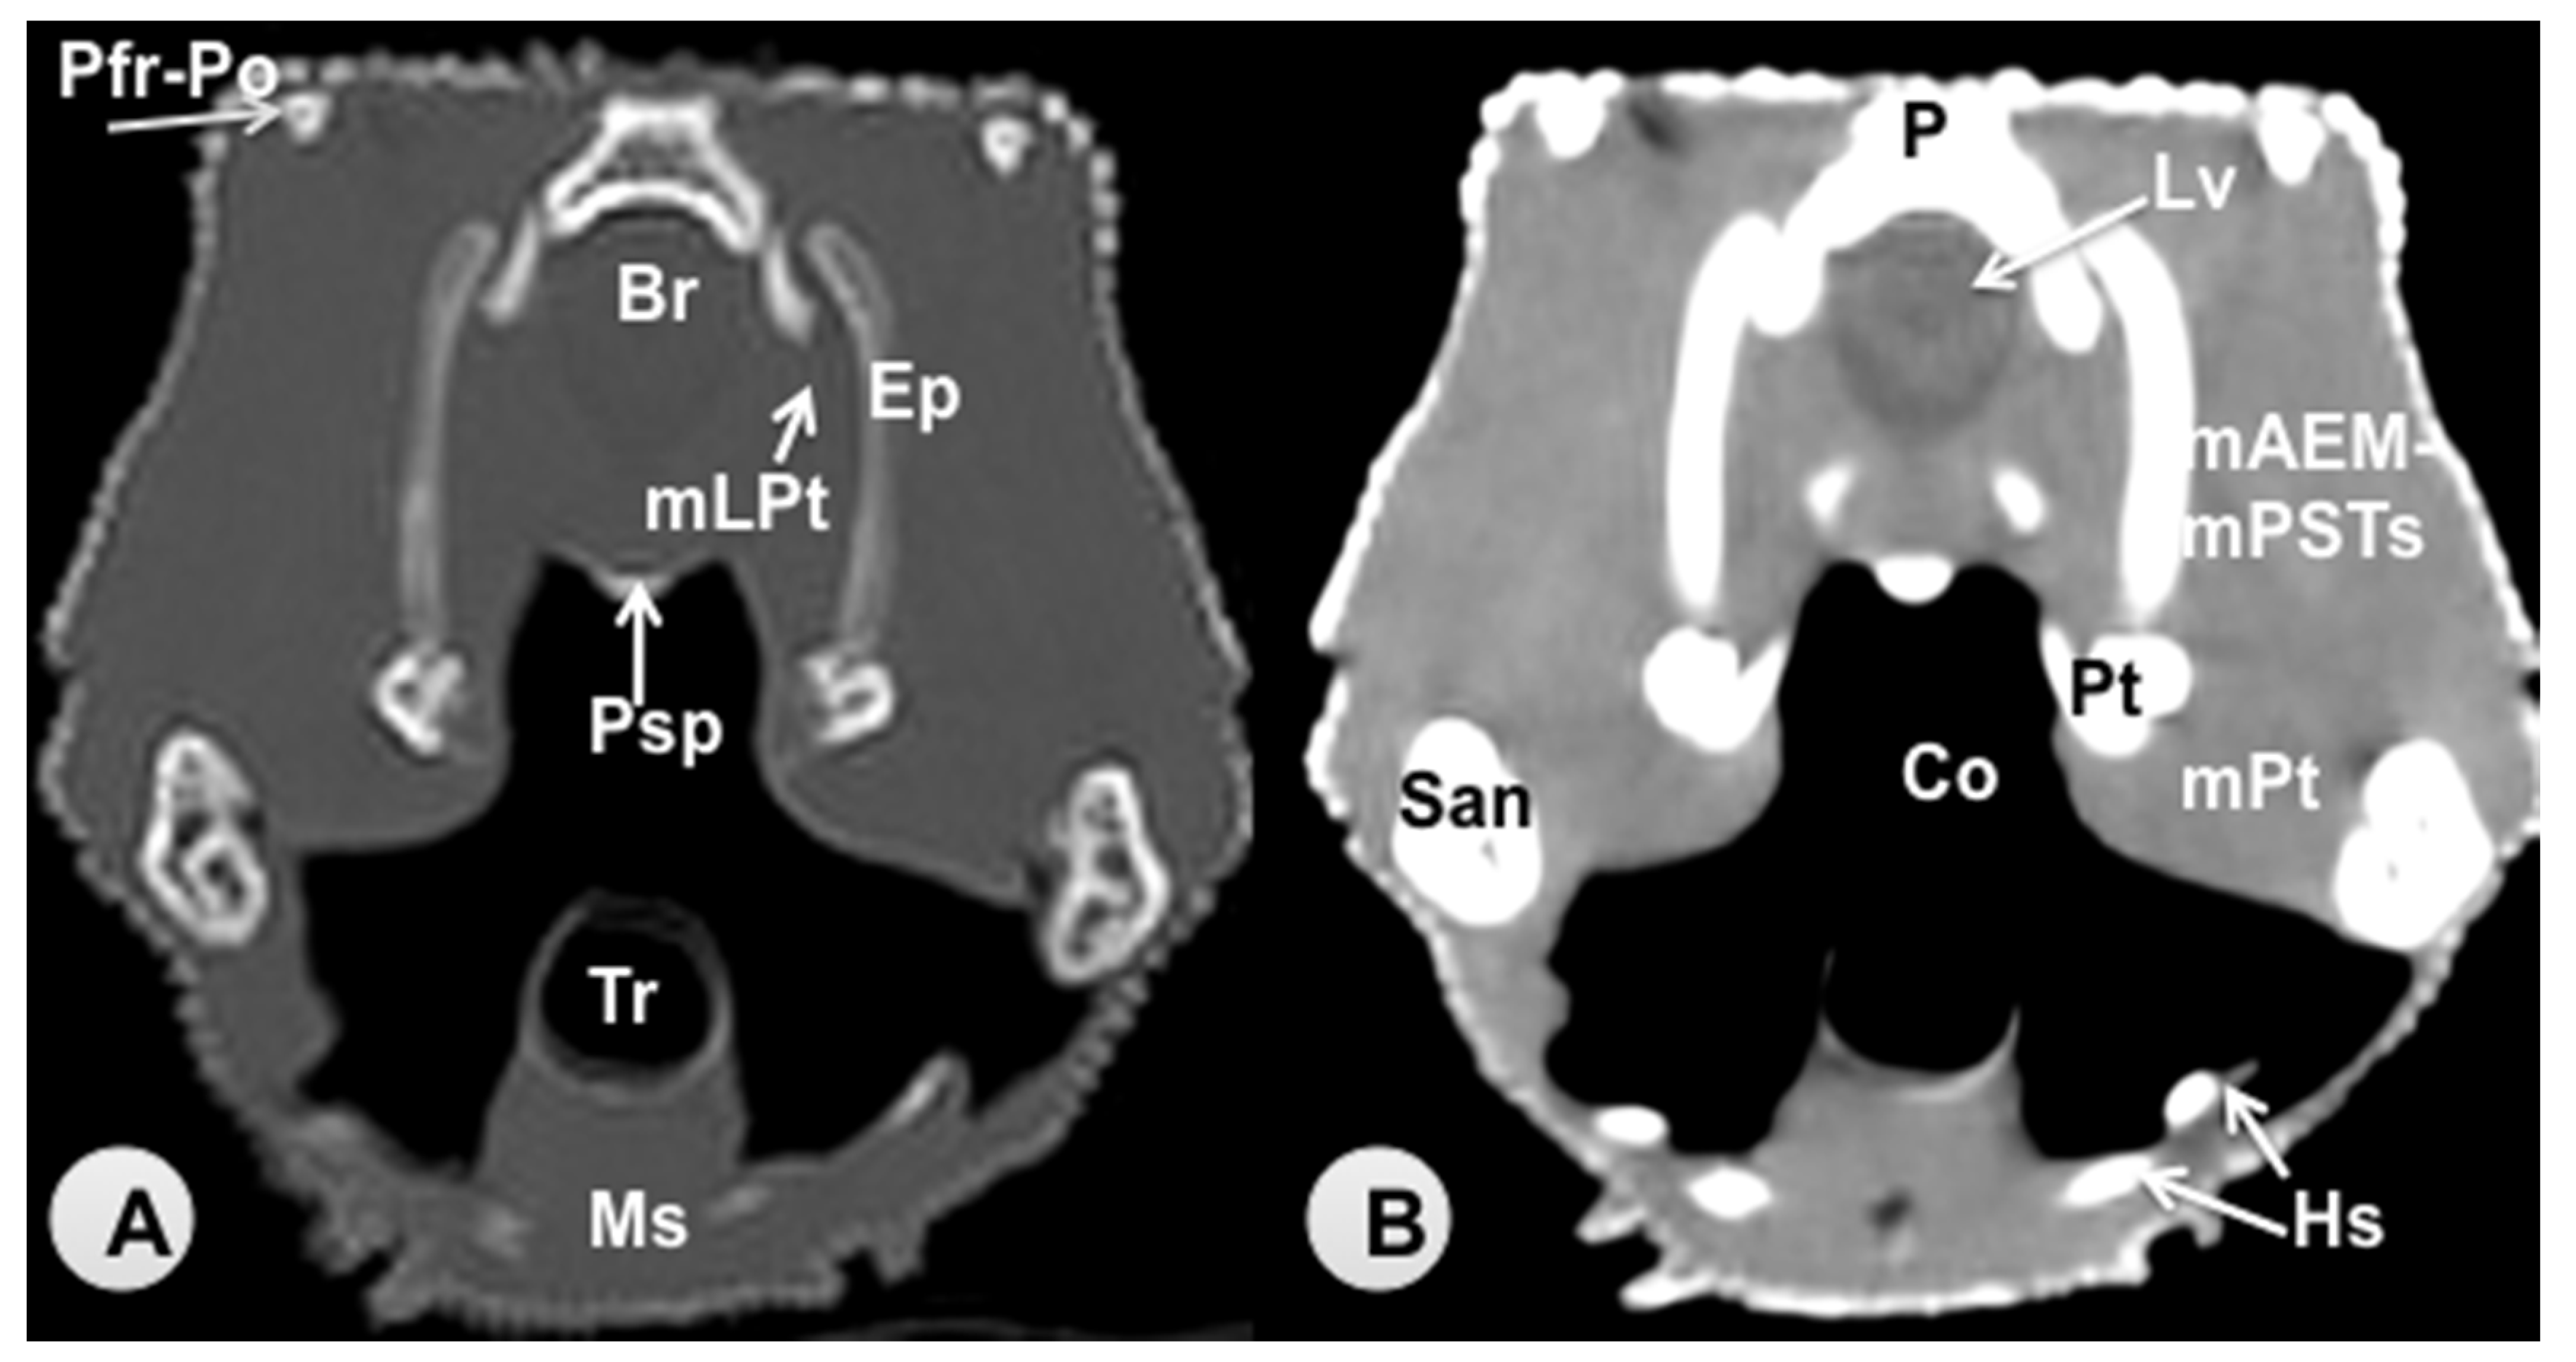

3.1. Transverse Computed Tomography Images